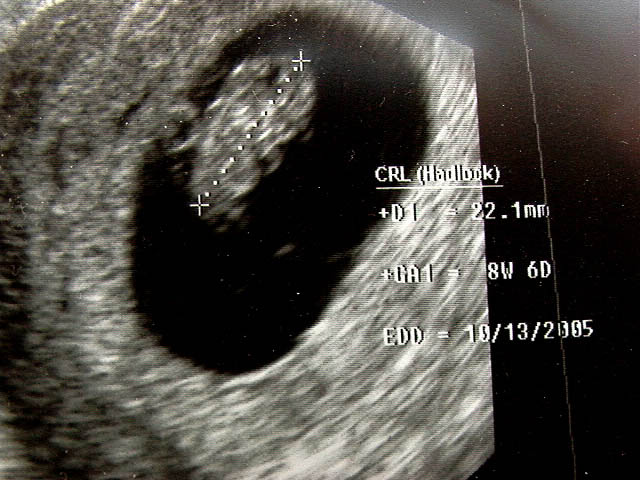

close up of the above image.